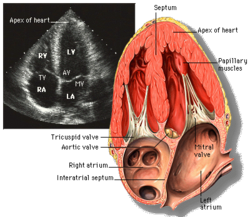

Apical four chamber ultrasound view of heart

Transthoracic echocardiography (TTE) uses ultrasonic waves for continuous heart chamber and blood movement visualization. It is the most commonly used imaging tool for diagnosing heart problems, as it allows non-invasive visualization of the heart and the blood flow through the heart, using a technique known as Doppler.

TTE is commonly used to evaluate patients with coronary artery disease.[4] Stress echocardiography is used to diagnose coronary artery disease and assess myocardial viability.[4]